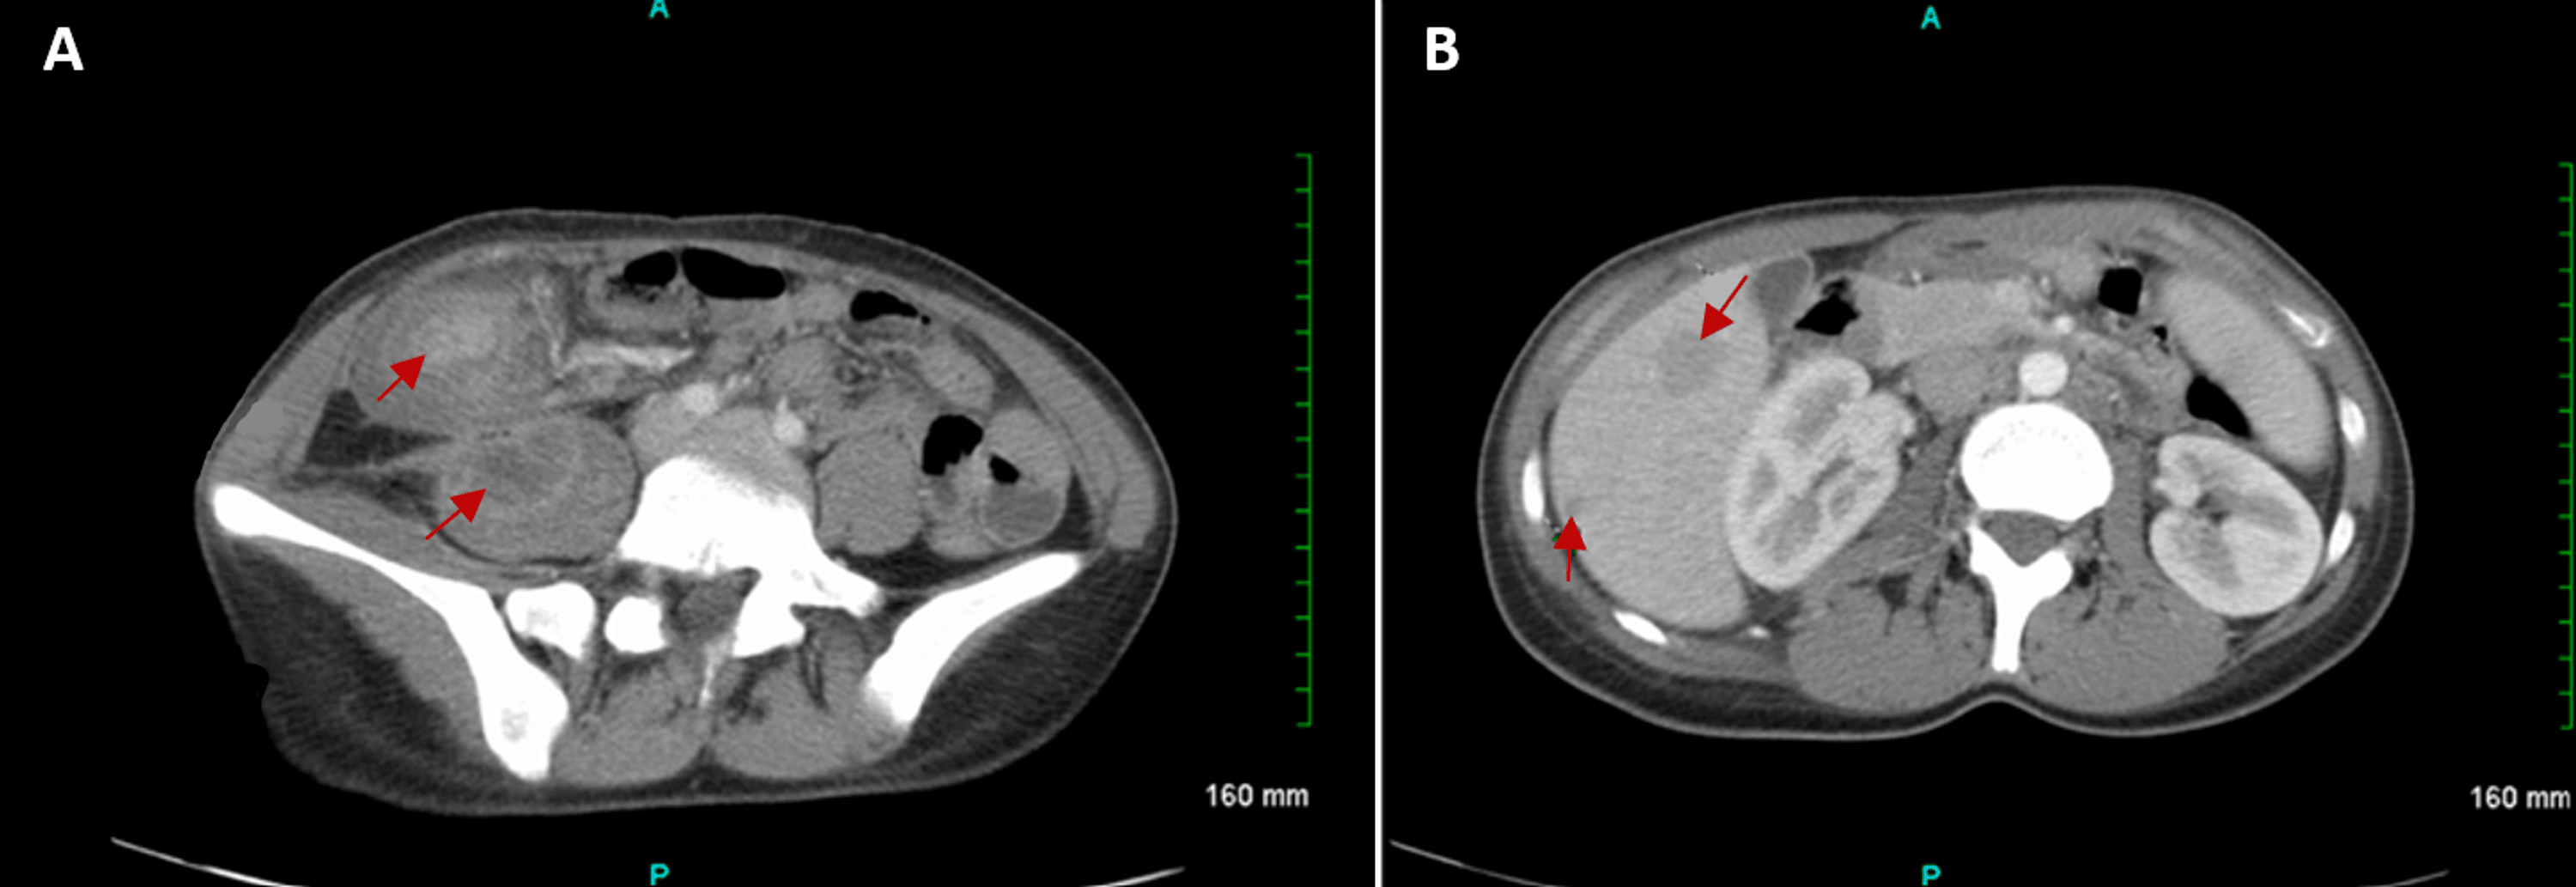

From www.cureus.com

Cureus Tumefactive Crohn's Disease Mimicking Colon Carcinoma in a Crohn's Disease Young Female Gaylyn henderson, mph, was diagnosed with crohn’s disease as a teenager and is sharing how the experience impacted her. Which children are at risk for crohn's disease? However, people assigned female at birth may be more likely to experience symptoms such as irregular periods, iron deficiency, osteoporosis, fertility issues, and pain during penetrative sex. Children and teens with crohn’s disease. Crohn's Disease Young Female.

Cureus Tumefactive Crohn's Disease Mimicking Colon Carcinoma in a Crohn's Disease Young Female Crohn's disease can occur at any age, but you're likely to develop the condition when you're young. Crohn's disease may happen at any age. Gaylyn henderson, mph, was diagnosed with crohn’s disease as a teenager and is sharing how the experience impacted her. However, people assigned female at birth may be more likely to experience symptoms such as irregular periods,. Crohn's Disease Young Female.